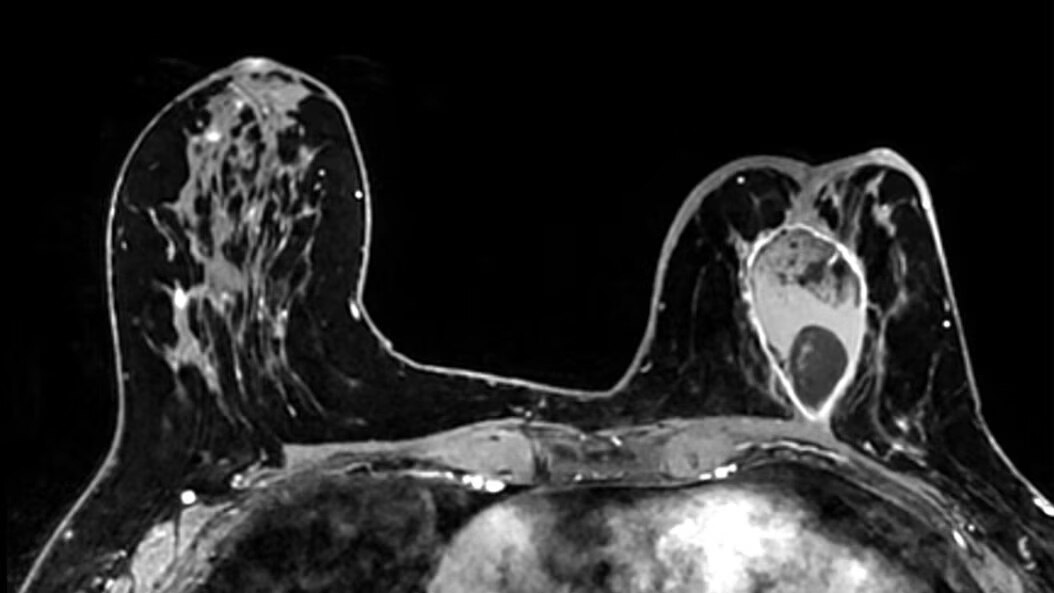

Body MRI for SIGNA

Discover Body MRI for SIGNA™. Capture detailed breast, abdominal, and pelvic anatomy with speed, flexibility and enhanced patient comfort.